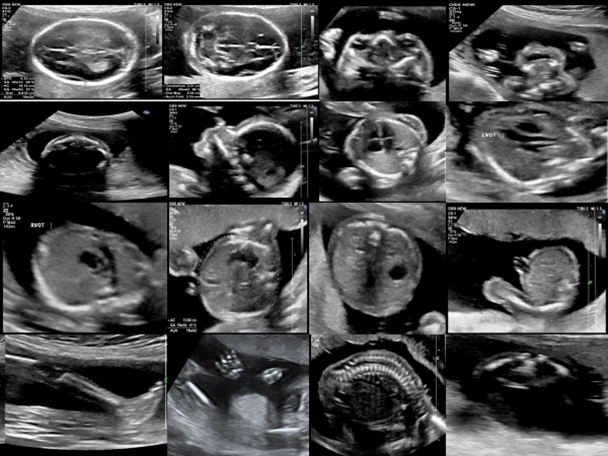

This is where Target Scan steps in, a revolutionary diagnostic tool designed to alleviate such burdens. Target Scan is not just another machinery; it is a bridge to understanding and healing. It addresses the primary concern faced by professionals like Dr. Mehta—accuracy in diagnostics.

In the ever-evolving landscape of healthcare, the need for accurate diagnostics is paramount. With Target Scan, practitioners can ensure that their diagnostic capabilities are not just meeting but exceeding expectations. The tool is designed to integrate seamlessly into existing operations, enhancing the facility’s capabilities without disrupting its workflow.